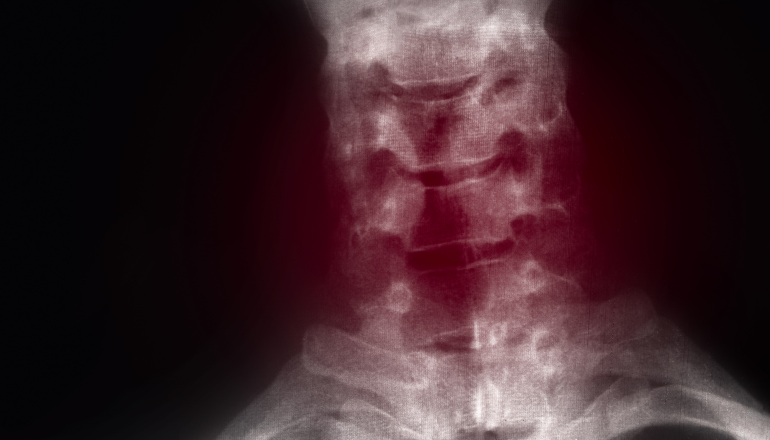

Cervical myelopathies and associated radiculopathy occur in approximately 1-2% of patients, over the age of 50. The transient symptoms and pain associated can significantly impact on a patients quality of life, affecting themselves as well as their families.